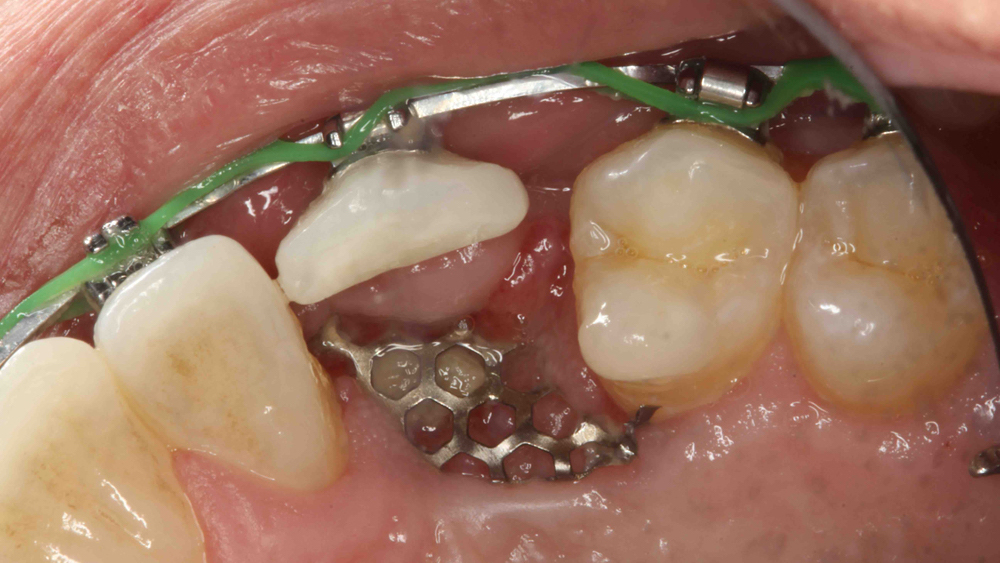

Titanium Mesh Membranes

Titanium mesh is a non-resorbable membrane that has been shown to be effective in maintaining space without collapsing. The membranes are flexible and can be bent and manipulated to form around the bony defect. The titanium mesh has demonstrated biocompatibility and features holes within the mesh, which allow for maintaining blood supply from the periosteum. The disadvantages of titanium mesh are increased wound dehiscence and difficulty in maintaining soft-tissue coverage (Figs. 4a, 4b). This may lead to increased infection and patient discomfort, which could lead to the necessity for early removal.

Figure 4a: Titanium mesh membranes have holes incorporated within the mesh

Figure 4b: Mesh exposure

Figures 4a, 4b: Titanium mesh membranes have holes incorporated within the mesh (4a), which allow for maintaining blood supply; however, these membranes have the disadvantage of increased wound dehiscence, which commonly involves exposure of the mesh (4b).